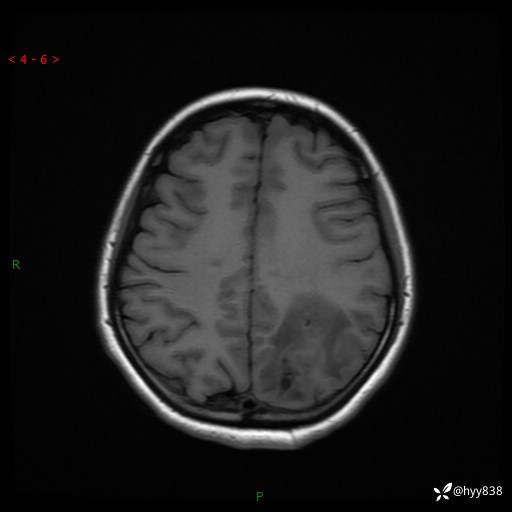

颅脑MRI平扫+增强